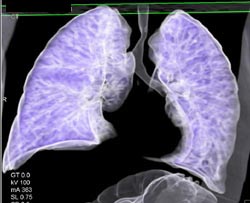

Airway Narrowing Due to Double Arch